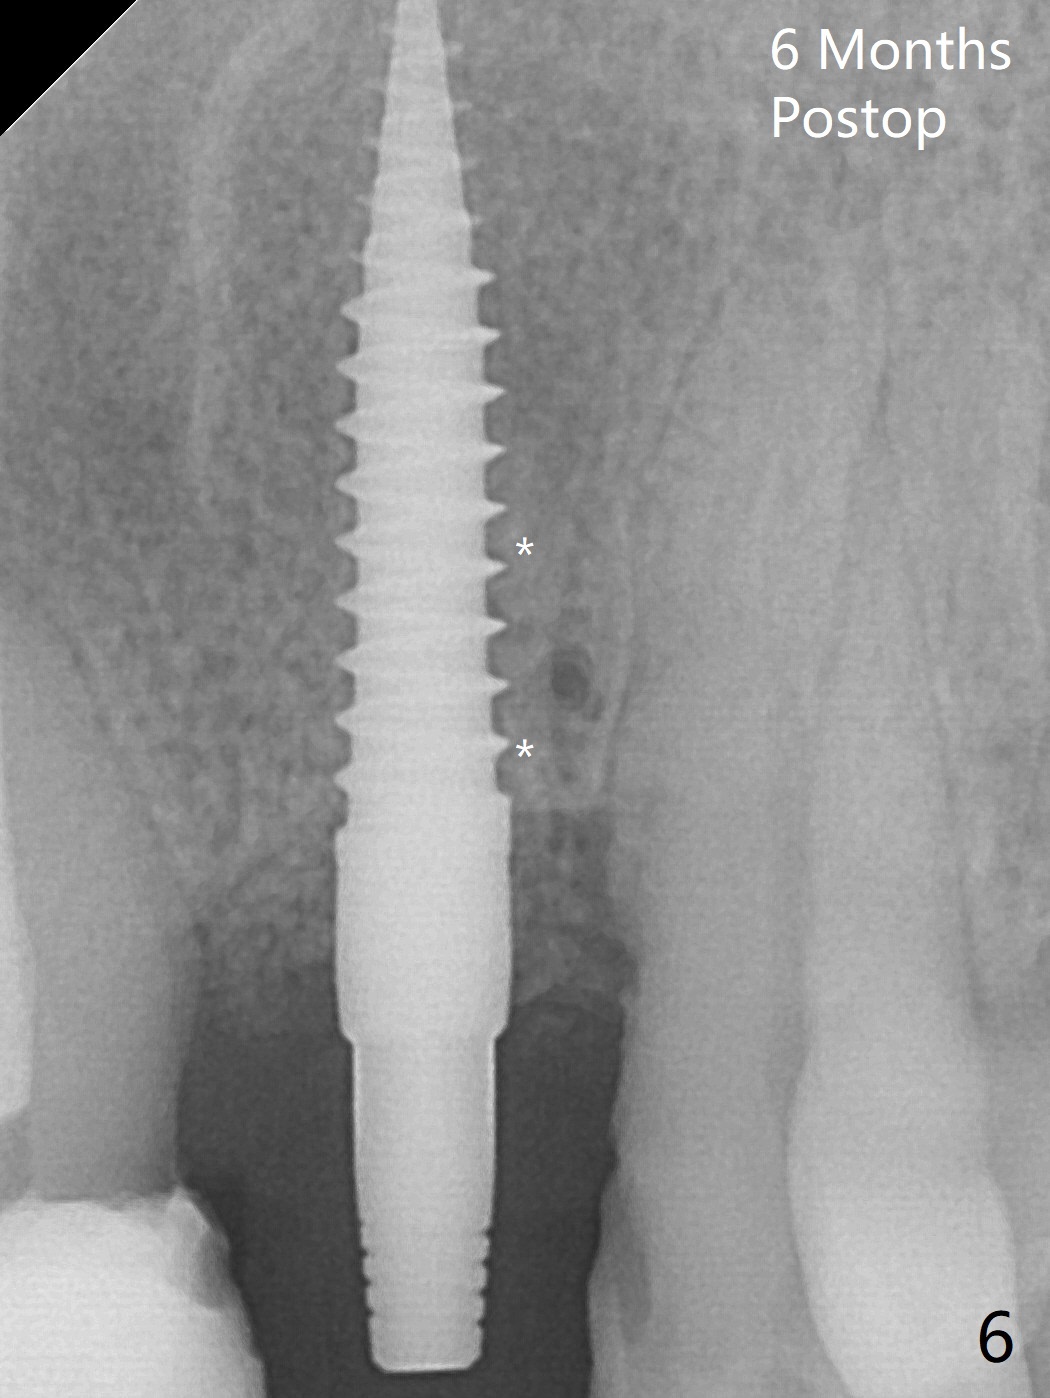

After curettage of the apical granulation tissue, a 3x16(2) mm 1-piece implant is placed with 20 Ncm because of slight overprep using 2 mm drill (Fig.3 (*: allograft)). The density of the bone immediately next to the implant threads increases 6 months postop (Fig.6 *).